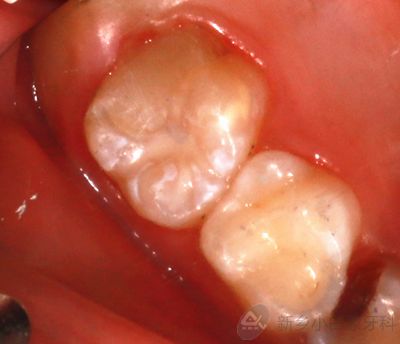

唐某某, 男,10岁,右上后牙有洞,进食时不适,于10月19日来诊。

检查:16远中邻合面龋坏达牙本质深层,探诊(-),叩诊(-),温度测试同正常牙,牙龈无红肿。

诊断:16深龋

1.png

治疗前